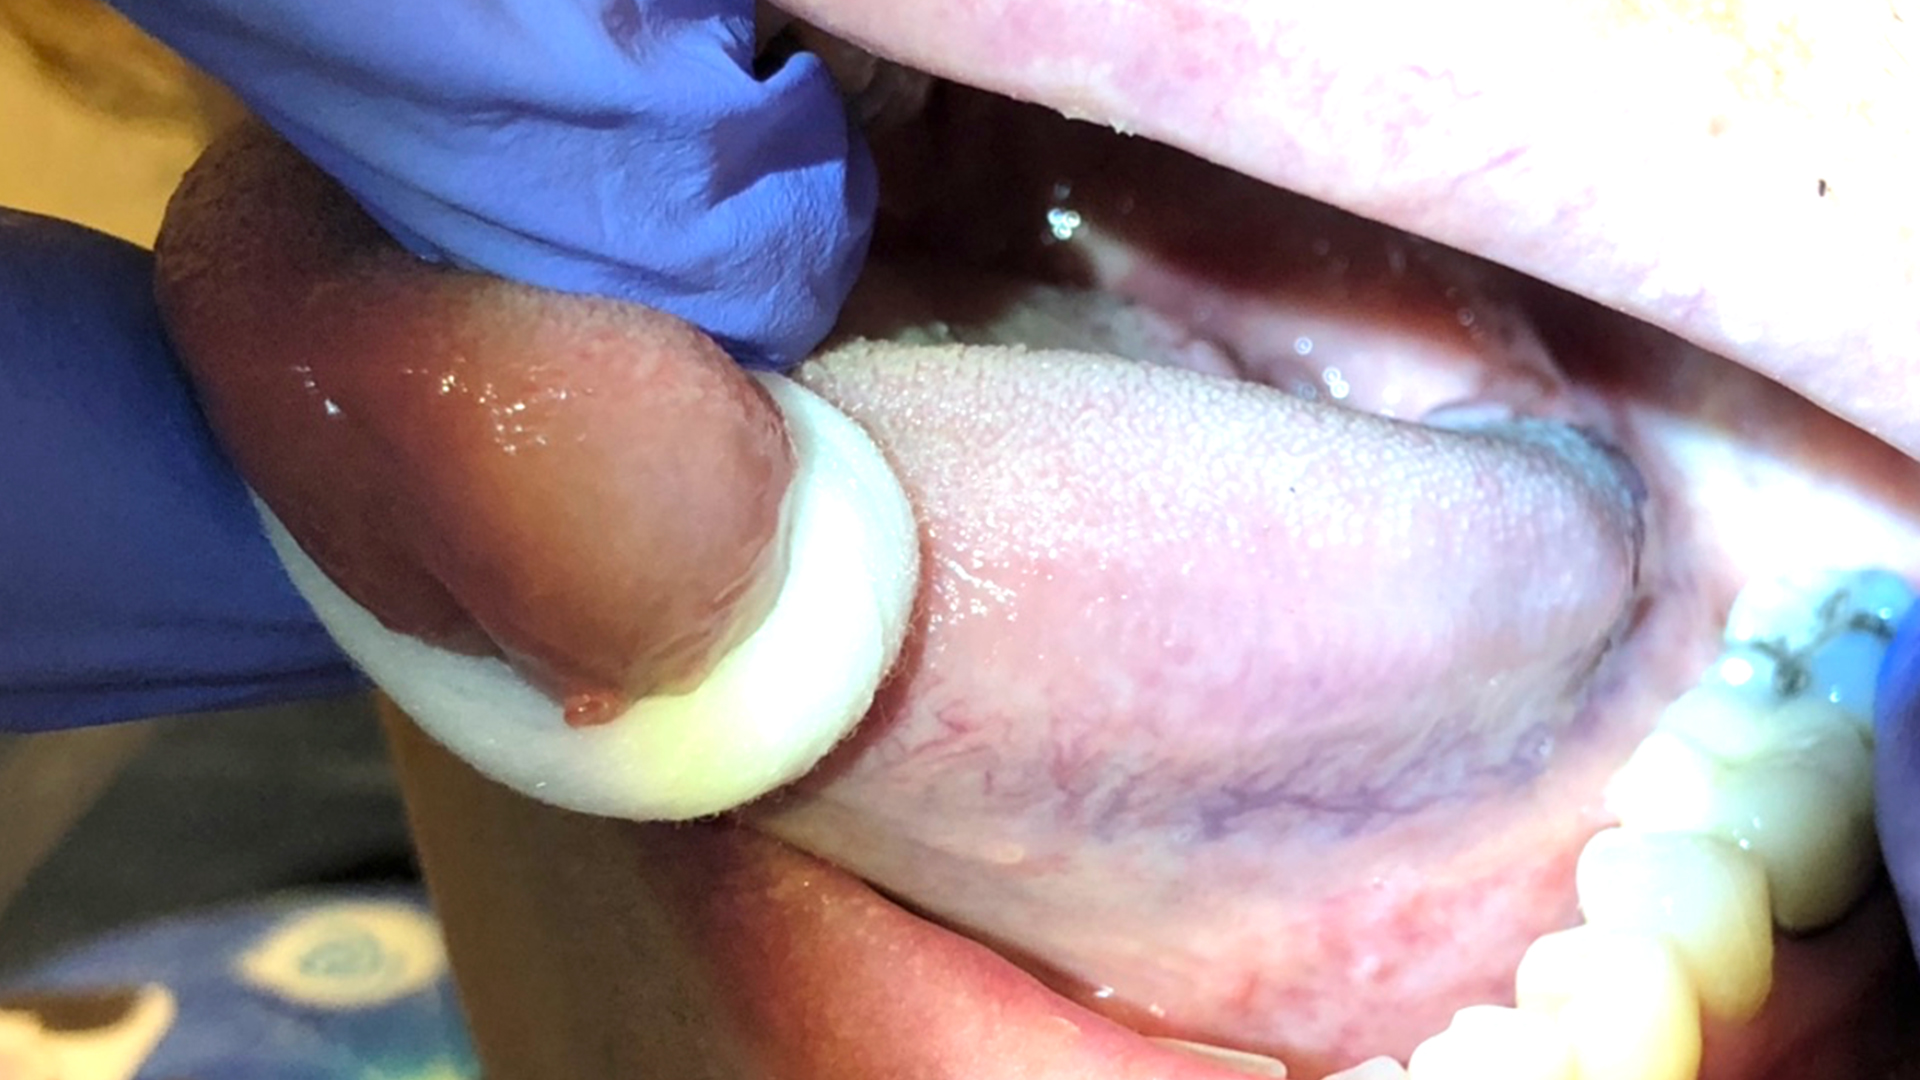

That Gut Feeling: Oral Manifestations of Gastrointestinal Inflammatory Conditions